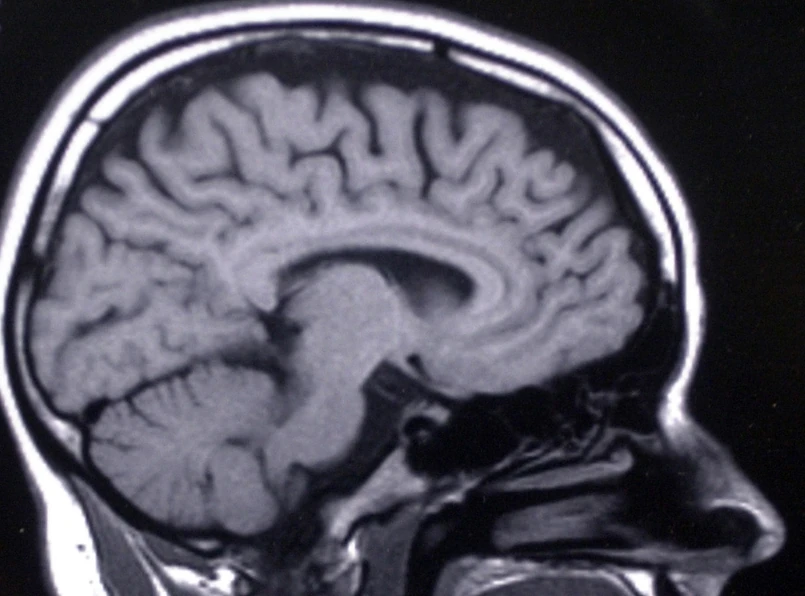

Co ma wspólnego orientacja seksualna z tym, jak pracuje mózg? Okazuje się, że bardzo wiele. Bo homoseksualni mężczyźni szybciej i dokładniej niż heteroseksualni przypominają sobie znajome twarze. Dlaczego? Bo, według naukowców, ich mózgi pracują, jak mózgi kobiet.

Okazało się, że homoseksualni mężczyźni w ten sam sposób co heteroseksualne kobiety korzystają podczas zapamiętywania i rozróżniania twarzy z obydwu stron mózgu. Dzięki temu mogą szybciej wykorzystać zapamiętaną informację. Heteroseksualni mężczyźni w tego typu zadaniach wykorzystują prawą półkulę mózgu i wypadają gorzej.

Różnice między osobami preferującymi prawą lub lewą rękę wykazały też badania części mózgu o nazwie ciało modzelowate (tzw. spoidło wielkie). Jest to struktura stanowiąca łącznik pomiędzy prawą i lewą półkulą mózgu. Kobiety i leworęczni mężczyźni mają większe ciało modzelowate niż praworęczni mężczyźni.

Zdaniem badaczy to właśnie budowa anatomiczna spoidła wielkiego tłumaczy różnice w rozpoznawaniu twarzy przez kobiety i mężczyzn o różnej orientacji seksualnej.